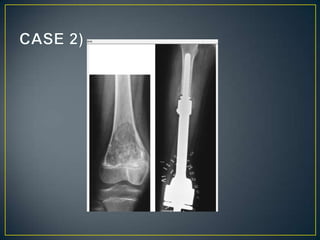

• Radiography is used mainly to document the results of

surgical resection of benign lesions such as osteoid

osteoma or to follow-up after curettage of benign tumors

or tumor-like lesions and application of bone gratfs. In the

case of malignant tumors, radiographic films permit one

to demonstrate the position of endoprostheses or bone

grafts in limb-salvage procedures.